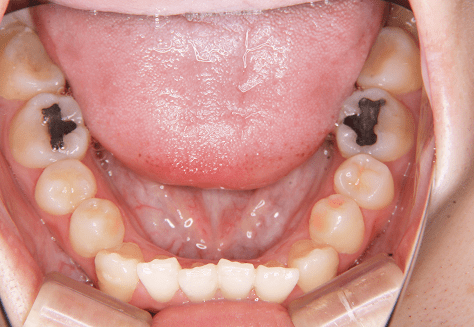

H.A

治療前

治療後

主訴

正中がずれているのが気になる。ちゃんと噛めていない。

診断

上下両側第二小臼歯先天欠如・上顎前突

年齢/性別

10代/女性

抜歯部位

必要に応じて乳歯抜歯

使用装置

6か月間エッジワイズにて下顎第一大臼歯の近心傾斜改善→上下インビザラインへ移行

保定装置

上下ビベラリテーナー

料金

初回資料採得・・・・・・・15,000円

診断料・・・・・・・・・・33,000円

動的治療終了時資料採得・・5,500円 -

基本料金

936,000円

診察料金

ワイヤー時:5,500円×4回

インビザライン時:1,100円×21回 -

治療期間

2年4カ月